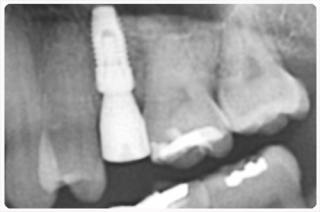

어금니 임플라늩 수술전후

임플란트 임상경력 19년의 김명섭 병원장님의 임플란트 수술 케이스.

김명섭병원장님의 임플란트는 [즉시 기능 임플란트]로, 발치후에 바로 임플란트를 심는 것으로, 사회생활에 불편함이 없도록 임플란트 기간을 혁신적으로 단축하였다.